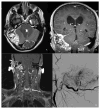

Intracranial Complications From Temporal Bone Cystic Angiomatosis